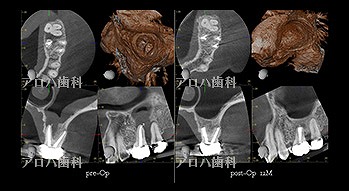

case4

再根管治療 2年予後

破折器具除去もあり

再根管治療の汚染の改善